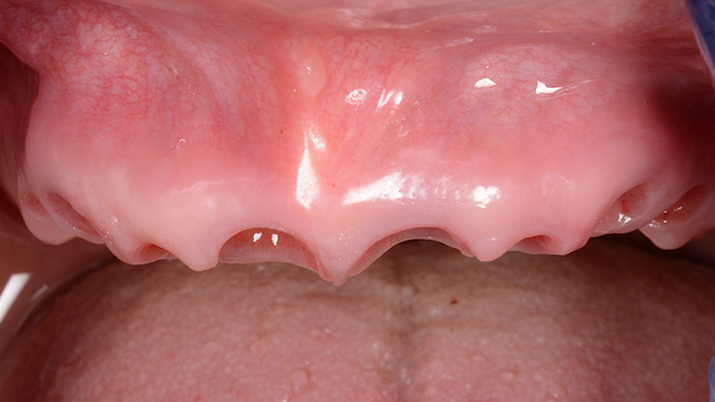

Clinical case: Extraction of all teeth in upper maxilla,

immediate implant placement, & provisionalization

- Courtesy of Dr. Iulian Filipov, Romania -